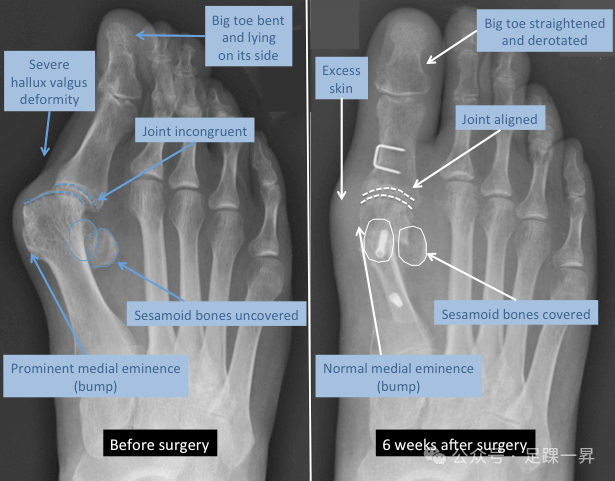

▲拇外翻手术前后X线表现变化。